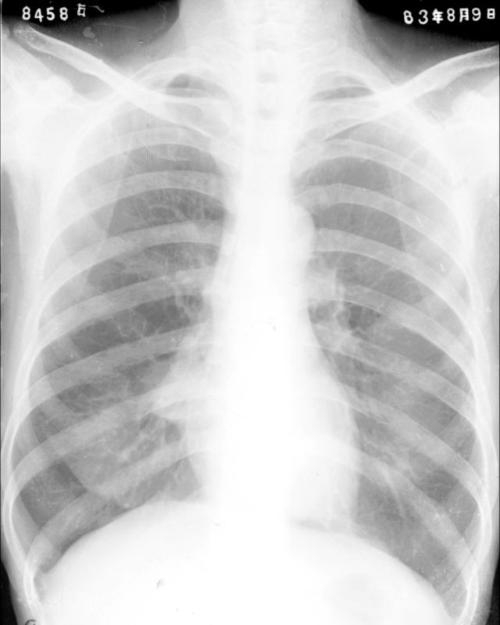

引起本综合征的病因大致有:非特异性炎症或结核性淋巴结肿大压迫,支气管扩张所致远端闭塞,黏液、脓栓或异物阻塞,支气管内膜结核或非特异性炎症致管腔狭窄或闭塞,支气管癌或良性肿瘤阻塞中叶支气管,原发性或转移性淋巴瘤肿大压迫。

中叶综合征(middle lobe syndrome)又称Brock综合征或Craham-Burford-Mayer综合征,是指由于支气管受管外肿大淋巴结的压迫阻塞,所致。